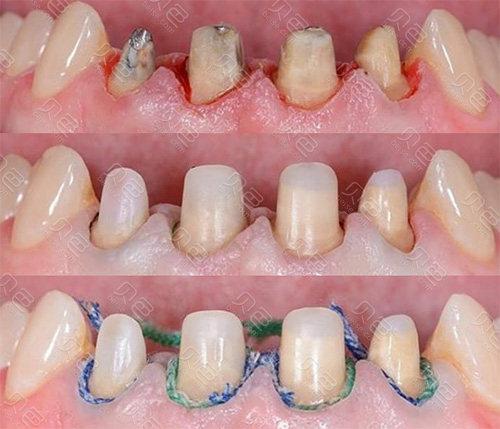

纤维桩的治疗过程相对简单,通常只需要进行局部后,在牙齿根部预先打孔,然后将纤维桩粘接在牙齿上。整个治疗过程较为快速,患者的不适感较小。

全瓷桩的治疗过程相对复杂,通常需要进行牙齿的磨牙、印模、制作桩体和修复体等多个步骤。由于全瓷桩的制作工艺较为精细,治疗过程相对较长,患者需要进行多次就诊。